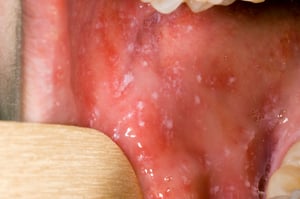

Koplik spots of the oral mucosa resemble grains of white sand surrounded by red areolae. These enanthems are pathognomonic and appear in 70% of patients (2). Koplik spots appear during the prodrome before the onset of the exanthem, usually on the oral mucosa opposite the first and second upper molars. They may be extensive, producing diffuse mottled erythema of the oral mucosa.

Koplik spots are classically described as being bright red spots with white or bluish-white centers that may resemble grains of sand. They may occur anywhere in the mouth, often precede the generalized exanthem, and are pathognomonic for measles (rubeola).